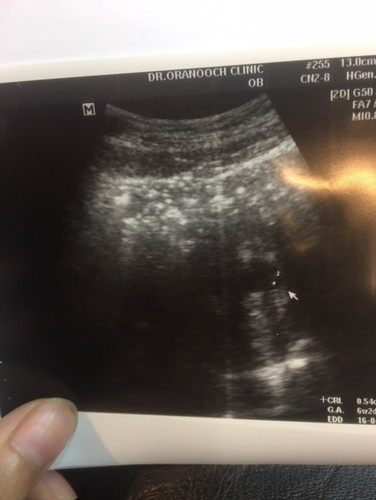

ถ้านับจากปจด วันแรก เราอายุครรถ์8w แต่ไปอัลตร้าซาว เห็นน้อง หมอคาดคะเนว่า น่าจะแค่6w 2วันเองคะ คุณแม่บ้านไหนเคยเป็นแบบนี้บ้างคะ

บ้านนี้เป็นคะครั้งแรกคลาดเคลื่อนไป1อาทิตย์กว่าๆ แต่พอซาวด์รอบสอง ตรงตามที่เรานับประจำเดือนคะ

เป็นค่ะ เพราะบางที ปจด ไม่ได้มาสม่ำเสมอค่ะ คุณหมอจะนับอายุครรภ์จากการอัลตร้าซาวค่ะคุณแม่ ☺️

เรื่องปกติค่ะ ไข่อาจจะตกช้าค่ะ ของตอนซาวด์ก็น้อยกว่าค่ะ พอเข้าช่วงเดือนที่3 ก็ตรงกันค่ะ

เป็นค่ะ เพิ่งไปตรวจมาวันนี้เลยค่ะ นับได้9w แต่ไปอัลตร้าซาวด์ ได้7w

เป็นเหมือนกันค่ะ อัลตร้าซาว 19w แต่ถ้านับจากประจำเดือน 21w ค่ะ

อายุครรภ์จริง ดูตามใบอัตตร้าซาวนะค่ะ เราก็เป็นเหมือนกันค่ะ